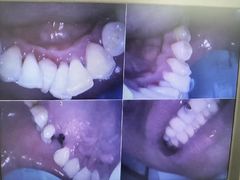

• 牙博士口腔品牌连锁(杨浦店)

• -牙博士口腔品牌连锁(杨浦店)